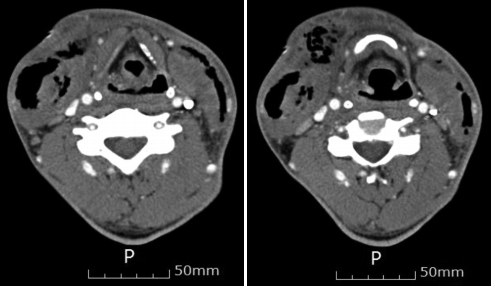

2. 66세 남자 환자로, 수일 전부터 지속되는 경부 통증, 고열, 삼킴 곤란의 증상으로 내원하였으며, 과거력상 heavy alcohol consumption 이외 특이 병력 없는 환자이다. 아래 설명 중 옳은 것을 고르시오.

해 설 괴사성 근막염은 당뇨, 전신 증상이 선생되기도 하며, 연부 조직에 gas를 형성한다. 근육과 다른 심부 조직은 일차적으로 침범하지 않으며, 림프절염과 지역적 림프절증은 드물다. 괴사 조직을 제거하는 중요하며, 항생제 병합요법을 사용한다. 합병증은 뇌신경증, 혈관미란, 질식, 종격동염이 있을 수 있으며, 치사율은 20~36%로 높은편이다.